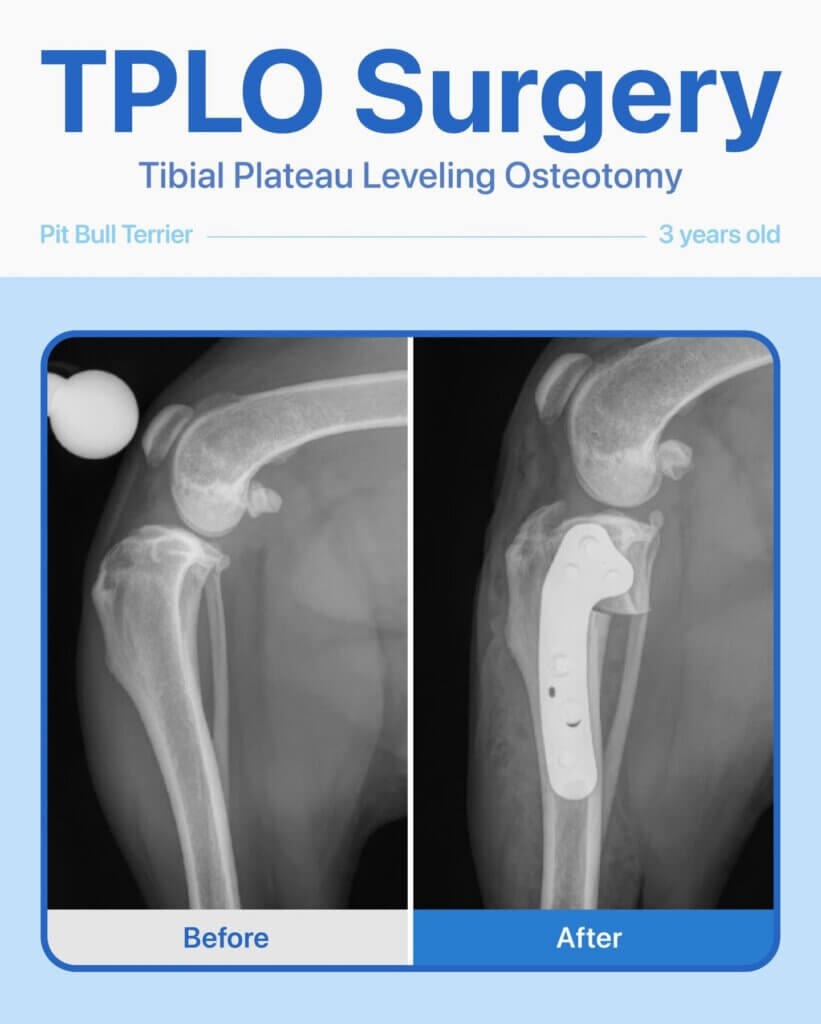

This 3-year-old female Pit Bull Terrier came to us unable to put weight on her left leg. Her owner wanted a second opinion, so we performed x-rays and a thorough orthopedic exam, which revealed a complete cranial cruciate ligament tear.

We recommended and performed TPLO surgery to stabilize her knee. Thanks to careful surgical technique and post-op care, she has made an amazing recovery — walking comfortably, running, and playing pain-free!